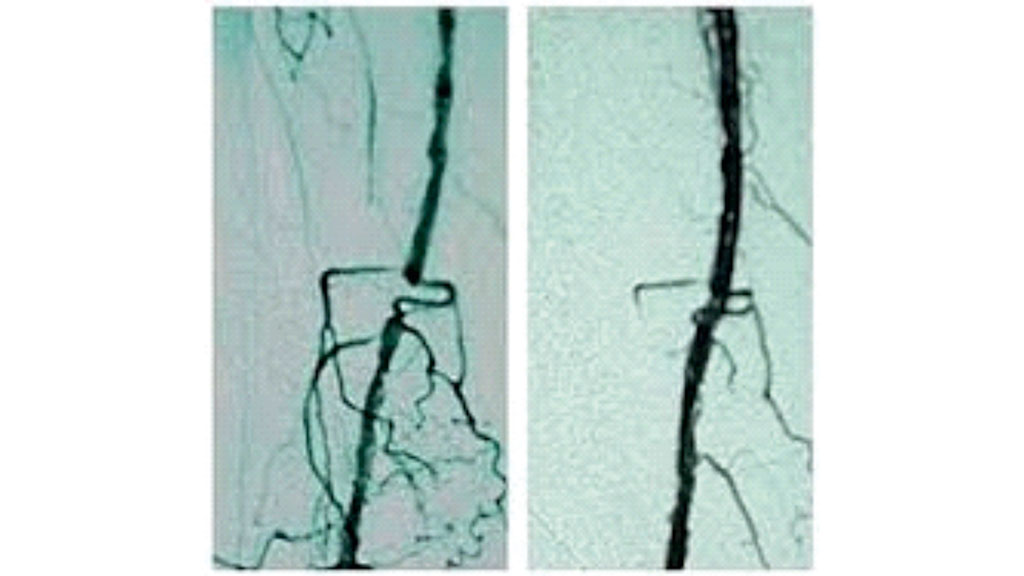

Eine Versorgung des Diabetischen Fußsyndroms erfolgt vorrangig durch die Gefäßchirurgie. Aber nur etwa 30 bis 40 % dieser Füße haben ein wirkliches therapeutisch anzugehendes Gefäßproblem (Angiopathie), welches durch verschiedene operative Maßnahmen wie das Ausschälverfahren (Desobliteration), die Bypasschirurgie (Vene oder Kunstprothese) und/oder die Kombination mit einem endovasculären Verfahren (z. B. Ballonerweiterung) korrigiert werden sollte (Abb. 1). Vorrangig sind beim Diabetes Veränderungen der Gefäße im Unterschenkel-Fußbereich charakteristisch, sodass insbesondere solche Verfahren eingesetzt werden sollten, die eine verbesserte Durchströmung in den kleinen Gefäßen erzielen (perkutane transluminale Angioplastie), ohne dabei einen zusätzlichen Weichteilschaden im Fuß-Unterschenkel zu erzeugen.